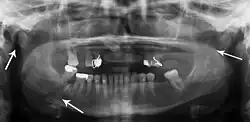

| 3D computed tomographic image of a mandible fracture in two places. One is a displaced right angle fracture and the other is a left parasymphyseal fracture. | |

Computed tomography is the most sensitive and specific of the imaging techniques. The facial bones can be visualized as slices through the skeletal in either the axial, coronal or sagittal planes. Images can be reconstructed into a 3-dimensional view, to give a better sense of the displacement of various fragments. 3D reconstruction, however, can mask smaller fractures owing to volume averaging, scatter artifact and surrounding structures simply blocking the view of underlying areas.

Panoramic radiograph of a simple mandible fracture of the right mandibular body, minimally displaced. Note that the teeth to the left of the fracture do not touch -